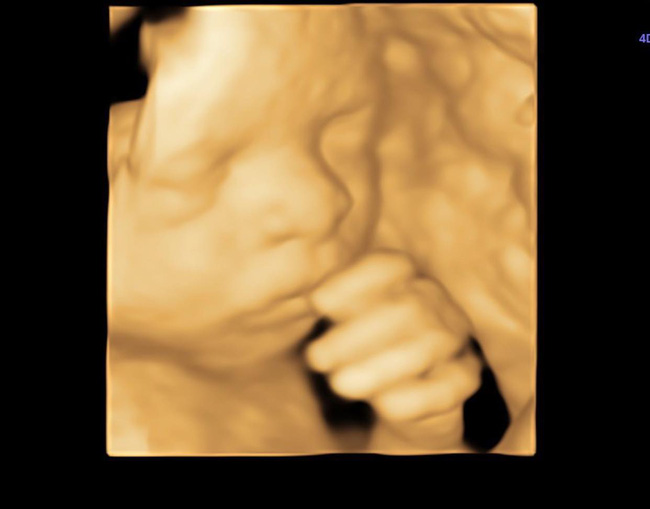

Mới đây, giọng ca sinh năm 1990 đã chia sẻ bức hình của thai nhi trong bụng qua siêu âm 4D và hài hước chia sẻ: "Người ta nói em đẻ con lai chắc đẹp lắm. Em đính chính là con em không lai mà nó rặt Ấn luôn nha bà con. Mẹ Việt đẻ con Ấn mới thật sự là hiếm có khó tìm nè".

Em bé của Võ Hạ Trâm có nhiều nét giống bố.

Trong hình, con gái của Võ Hạ Trâm trộm vía trông đáng yêu và đúng là có rất nhiều nét giống bố. Nhiều bạn bè, người hâm mộ của Võ Hạ Trâm cũng phải công nhận điều đó và bình luận hài hước: "Đẻ thuê rồi chị ơi", "Thôi chỉ còn hy vọng giống mẹ ở giọng hát"...